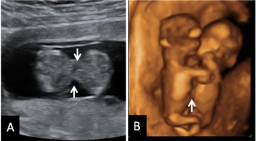

Se trata de un acúmulo de líquido que se localiza en la parte posterior del cuello y dorso fetal. Este acúmulo de líquido existe en todos los fetos, pero es mayor en los que tienen síndrome de Down u otras alteraciones cromosómicas. También se ha visto que puede estar aumentado en fetos con otras alteraciones, cardiacas, como ejemplo [ Ver ecografía del pliegue nucal ]